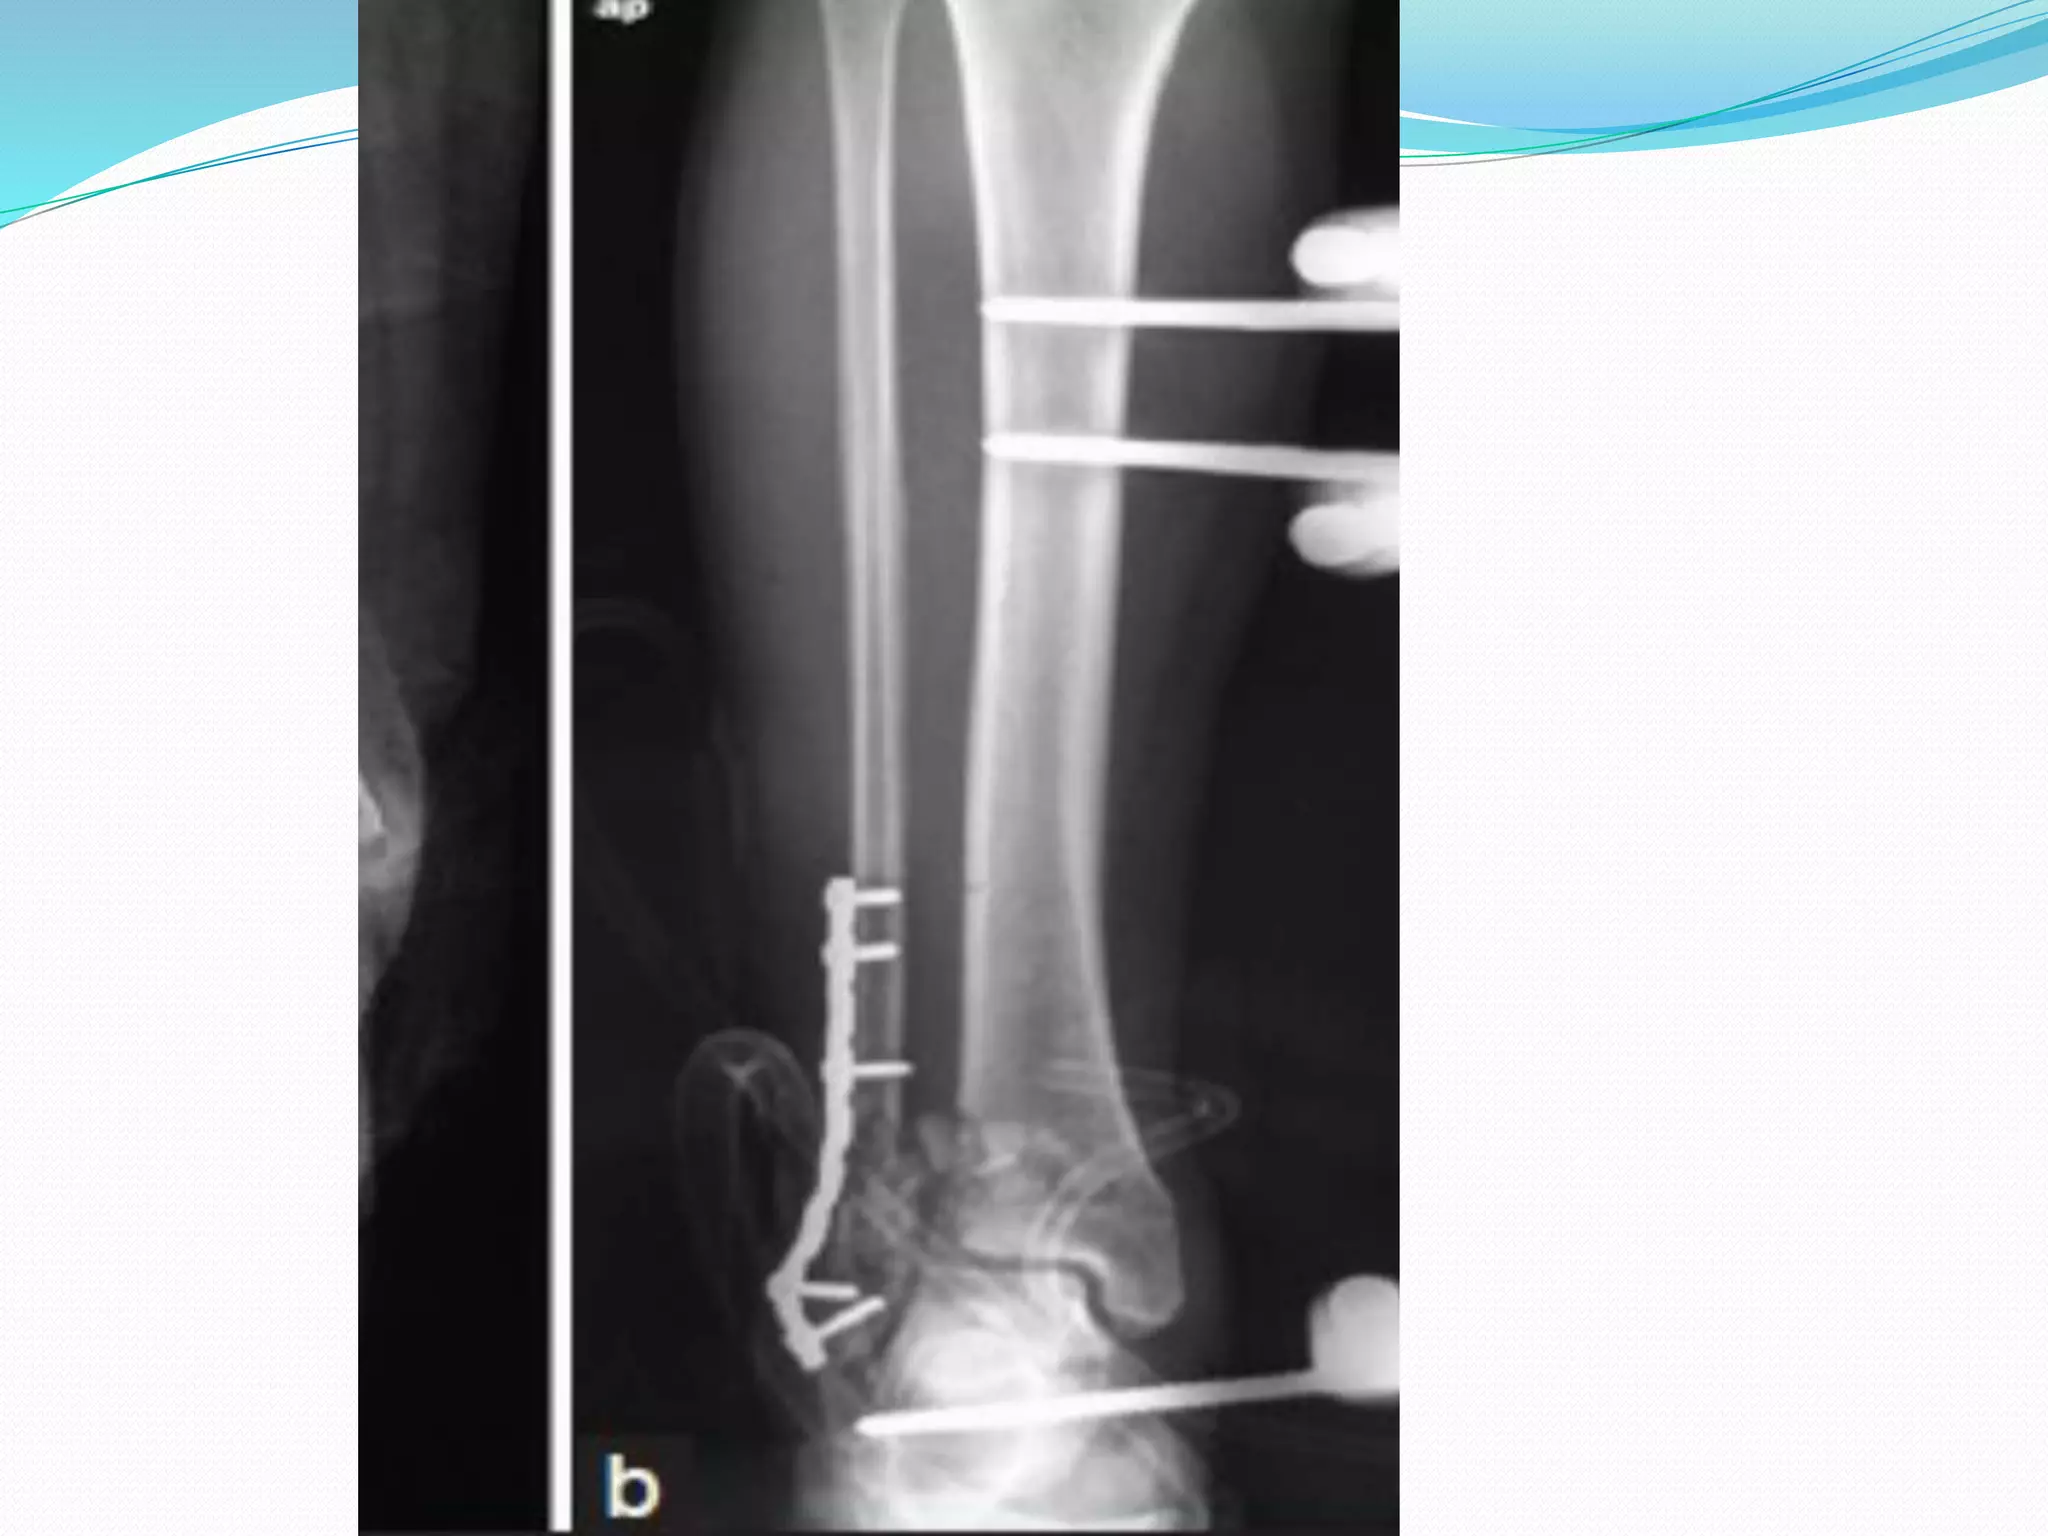

TWO STAGE PROTOCAL

 All B3 and C type 0f

AO/OTA

 Ruedi & Allgower type 3

 1. Fix the # fibula(90%)

through postero lateral

approach to regain the

correct lengh of the tibia

and facilitate three

dimensional view of the

fracture

 2.External fixator-

a)Ankle Spanning -rigid

-articulated

b) Non spanning -

illizarov

-hydride

First step